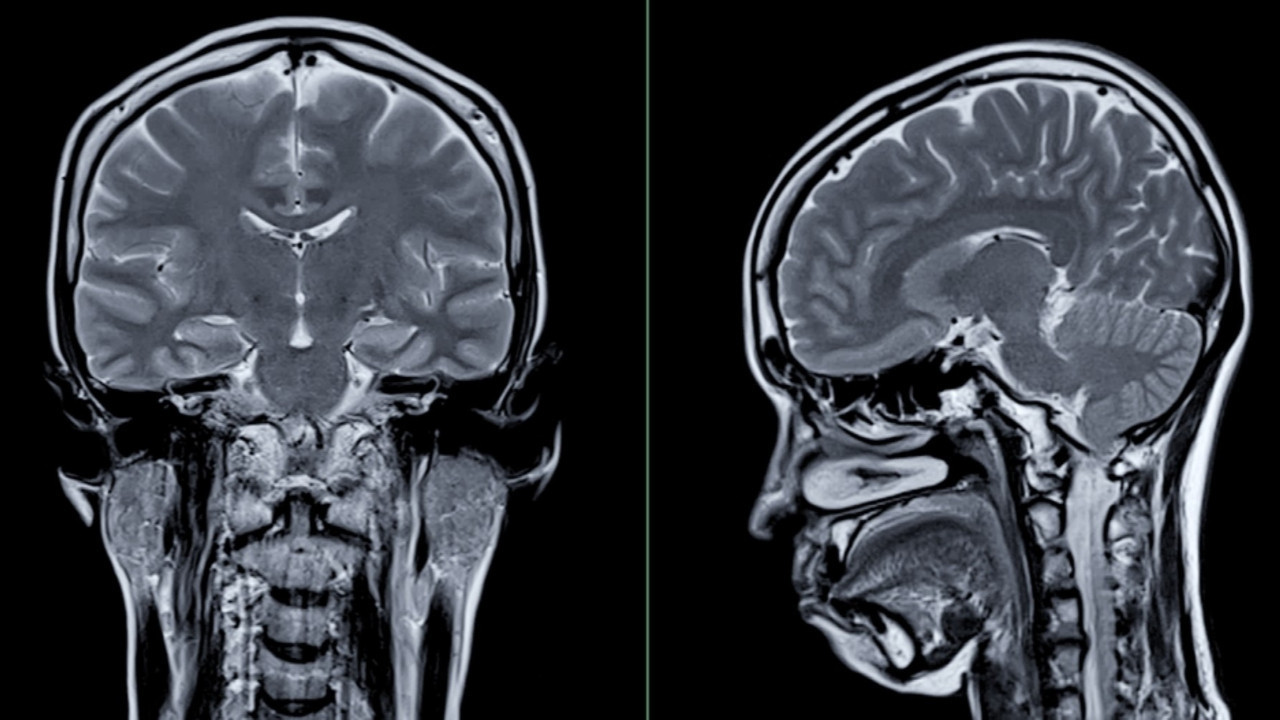

Analizler sonucunda beynin cinsiyete bağlı küçülme hızının belirli bölgelerde farklılık gösterdiği saptandı. Erkeklerde yaşlanmayla birlikte beynin daha fazla bölgesinde hacim kaybı görüldü.

Kadınlardaysa erkeklere kıyasla daha az bölgede küçülme saptandı, ayrıca beyin korteksinin kalınlığının daha az değiştiği tespit edildi.

Kadınlar Alzheimer hastalığına erkeklerden iki kat daha fazla yakalanıyor. Bu durumun kadın beyninin daha hızlı küçülmesinden kaynaklanabileceği düşünülüyordu. Ancak bulgular tam tersine kadın beyninin genel olarak daha yavaş hacim kaybettiğini gösterdi.

Araştırmanın yazarlarından nörobilimci Anne Ravndal, "Eğer kadınların beyni daha hızlı küçülseydi Alzheimer'a yakalanma oranları açıklanabilirdi. Ama veriler bunun aksini gösteriyor" dedi.

Araştırmada beynin öğrenme ve hafızadan sorumlu merkezi hipokampüste cinsiyete bağlı herhangi bir farklılık gözlemlenmedi.